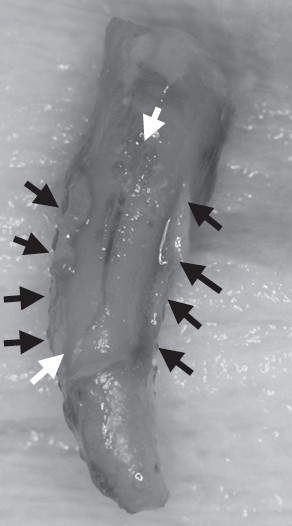

図 48時間おきにウェッジを入れ替え繰り返しの外傷を

加える実験でも歯周炎の進行に影響しなかった。